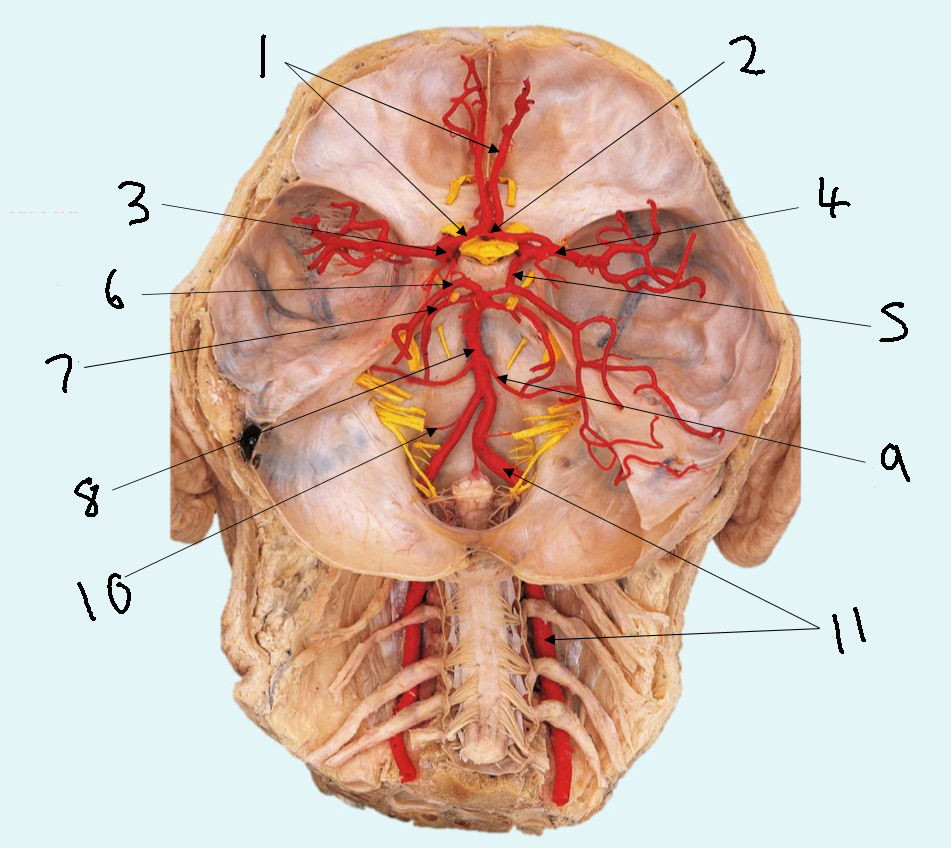

What is 1?

anterior cerebral artery

What is 2?

anterior communicating artery

What is 3?

internal carotid artery

What is 4?

middle cerebral artery

What is 5?

posterior communicating artery

What is 6?

posterior cerebral artery

What is 7?

superior cerebellar artery

What is 8?

basilar artery

What is 9?

anterior inferior cerebellar artery

What is 10?

posterior inferior cerebellar artery

What is 11?

vertebral artery